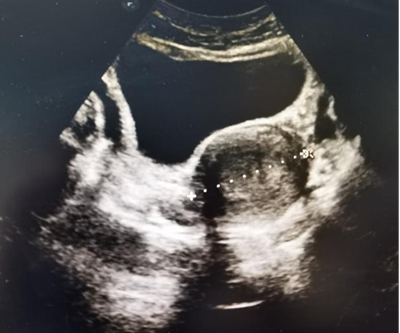

患者于入院前半年因无明显诱因出现阴道流血,遂就诊于我院,行妇科B超提示:子宫内膜占位性病变;行宫腔镜检查提示:宫腔布满结节状病灶,质地糟脆,考虑子宫内膜癌,宫颈未受累;宫腔镜下活检病理提示:低分化子宫内膜样腺癌;现患者为求进一步治疗,就诊于我院,我科以“低分化子宫内膜样腺癌”收住。